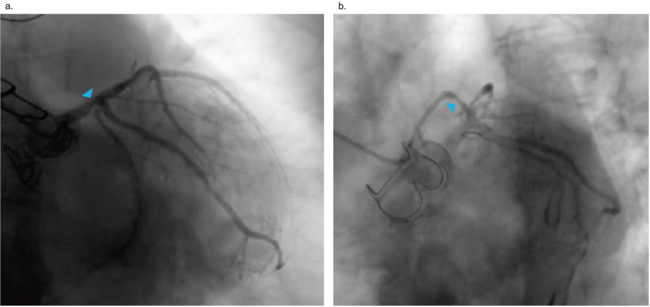

Baseline characteristics of the 10 patients are summarized in Table 1. Eight patients were octogenarians, and the other 2 patients were selected for the hybrid procedure due to their intermediate to high surgical risks. Five patients had LMCA disease, including 3 with multivessel disease. In addition, 5 patients had proximal LAD disease, 2 of whom had multivessel disease. The SYNTAX scores ranged from 13 to 35.5, and 5 patients had a SYNTAX score greater than 22 (Table 2). The Figure shows the coronary angiography of a patient with LMCA bifurcation and LAD disease (case 7). Table 2 summarizes coronary revascularization characteristics of the patients.

The median hospital length of stay after CABG was 5 days, including 2 patients who underwent TAVR during the same admission for CABG. The interval between CABG and TAVR ranged from 3 days to 5 months. During the interval, 1 patient (case 8) required hospitalization for acute heart failure — which was stabilized with medical management, including hemodialysis — and underwent elective TAVR. TAVR characteristics are summarized in Table 3. In this cohort, all patients underwent transfemoral TAVR under conscious sedation, with 1 patient receiving a valve-in-valve procedure for prosthetic aortic valve stenosis (case 7). This patient required a second valve due to the malposition of the first transcatheter valve. The Sapien 3 valve was used in 5 patients, and the Evolut Pro/Pro+ valve was also used in another 5 patients. Seven patients were discharged home on post-procedural day 1, and the remaining patients who experienced conduction disturbances and required permanent pacemaker implantation after TAVR were discharged on post-procedural days 2 and 3. All patients improved to New York Heart Association class I/II heart failure symptoms at 1-month follow-up. During follow-up, 1 patient with end-stage renal disease (case 8) died suddenly 43 months after TAVR, and 2 patients died of non-cardiovascular causes (24 and 34 months, respectively). All patients survived at least 15 months after TAVR, and none required additional coronary revascularization.